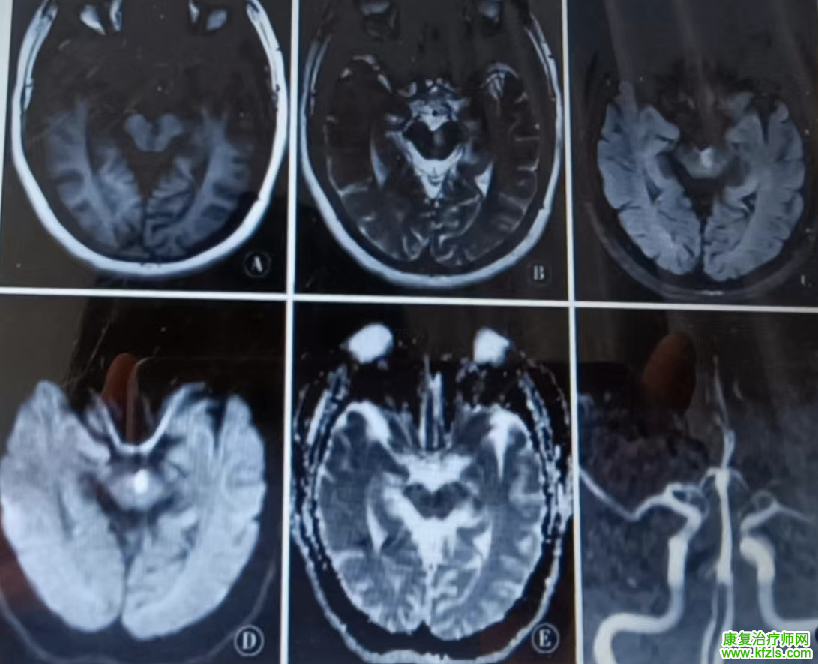

52 岁男性,既往「高血压」病史,以「头晕伴言语不清、口角歪斜 15 d」为主诉入院,患者 15 d 前无明显诱出现头晕,伴恶心、呕吐、全身出汗,未诊治;后症状逐渐加重出现视物重影、言语不清、饮水呛咳,查体:构音障碍,双眼球左右运动不能,上下运动正常,无眼震。右侧额纹消失,右眼闭目无力,右侧鼻唇沟浅,示齿口角左偏,右侧鼓腮漏气,Romberg 征(+),走「一」字不稳。头颅核磁提示双侧脑桥被盖部梗死:

脑干梗死

病例来源:参考文献